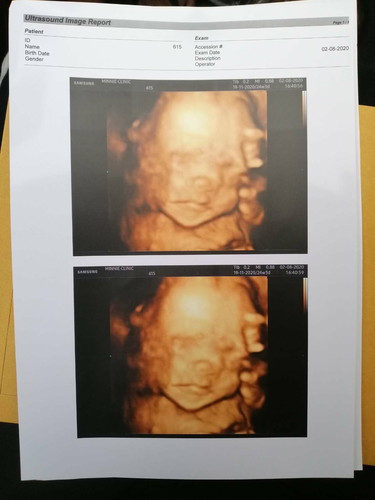

24+3

24 + 3 weeks กำหนด ประมาท 19-11-2020 ใคร ทีมเดือน พ.ย มาโม้ลูกกันหน่อย ^^